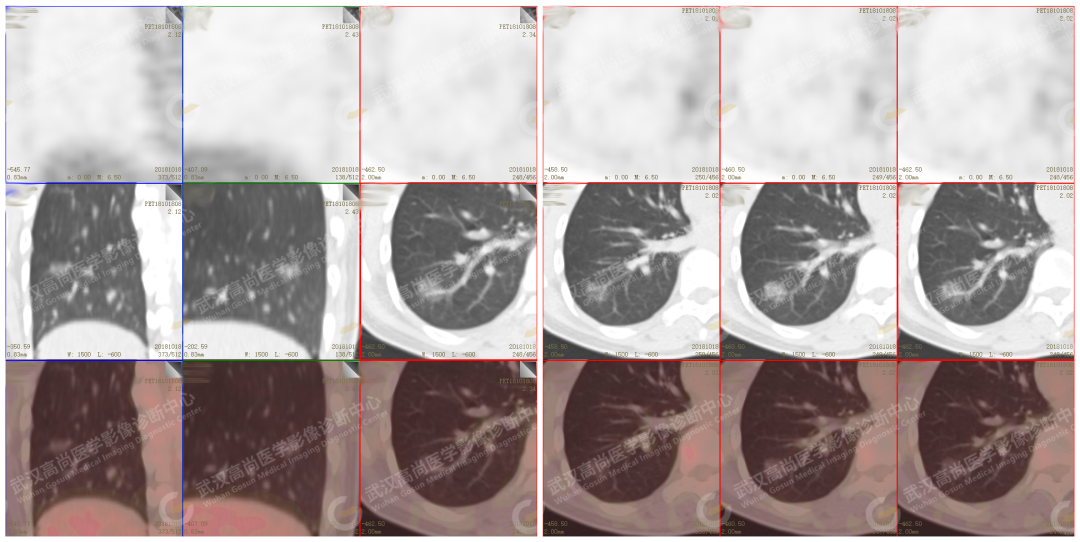

PET/CT 示 : 右肺下叶外基底段纯磨玻璃结节(pGGN),代谢未见增高

CT 示 : 浅分叶,可见支气管及粗大血管穿行其中 , 磨玻璃边缘清晰

CT 示 : 浅分叶,可见支气管及血管穿行其中 , 磨玻璃边缘清晰